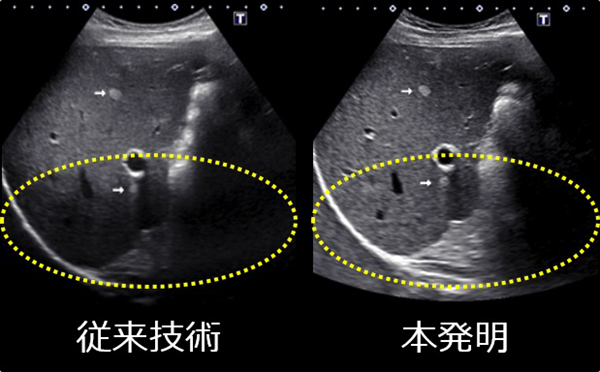

本技術は,従来は映像化できなかった深部の組織を高解像度で映像化する技術で,超音波診断装置の基本性能を飛躍的に向上させることができた。本技術により病変の早期発見が期待できると共に,胃や腸などの消化管や筋肉・腱の高解像度の影像化を実現した。キヤノン製超音波診断装置のラインアップには「Differential-THI(Differential Tissue Harmonic Imaging)」として本技術を搭載している。

従来技術と本発明の超音波画像